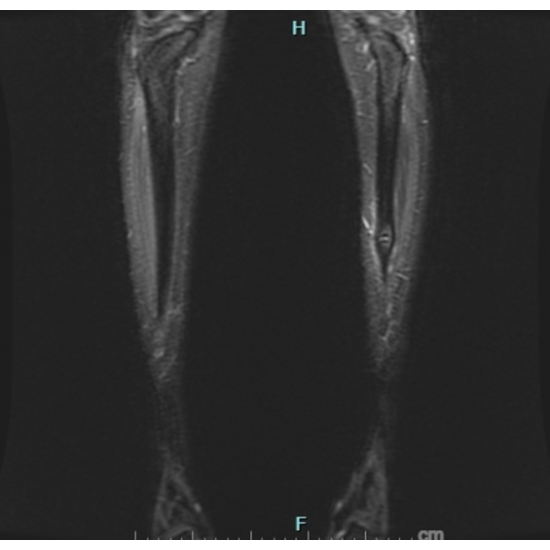

| Hoop Dreams And Bone Nightmares - Page #3 | |||